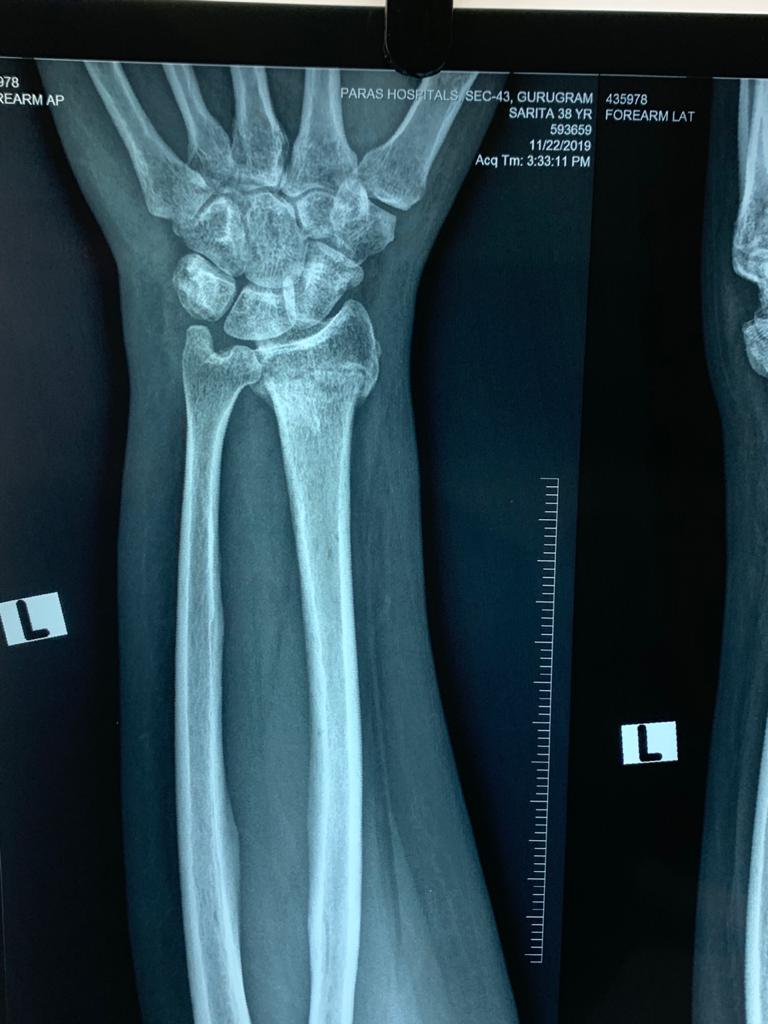

Preop Xray of an osteoporotic wrist fracture

osteoporosis

Postop xray of the fracture fixed with plate